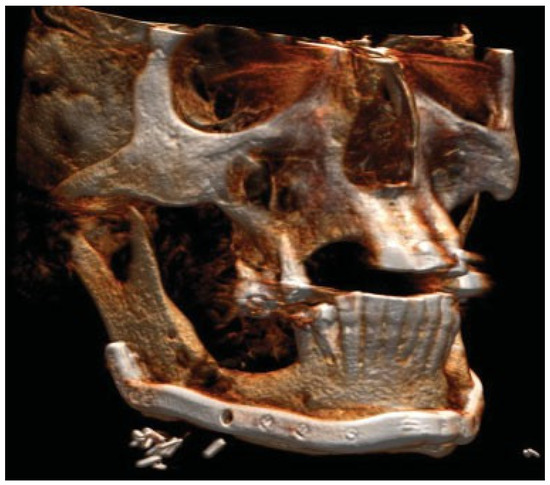

Figure 3.

Patient developed infections with oral mucosal fistulas in the fracture areas and an open bite. CBCT displays obvious anterior rotation of proximal segments and posterior rotation of the dentate part of mandible. Considerable muscle action creates new dislocation and is not counteracted by the inadequate osteosynthesis of the fractures.